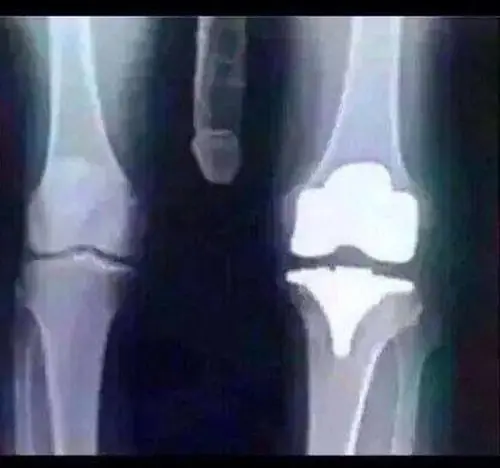

Me tomaron radiografìas,

mientras te llevan de una secciòn a otra del hospital inmovilizado no logras ver a los lados , sòlo ves las personas cuando te miran a la cara y sòlo ves el techo, como en las pelìculas y series.

al ver q' no tenìa daños en el cuello me quitaron el collarìn, me pusieron antidolorìficos por vìa intravenosa, estuve todo el puto dìa en el hospital, estaba hecho mierda.